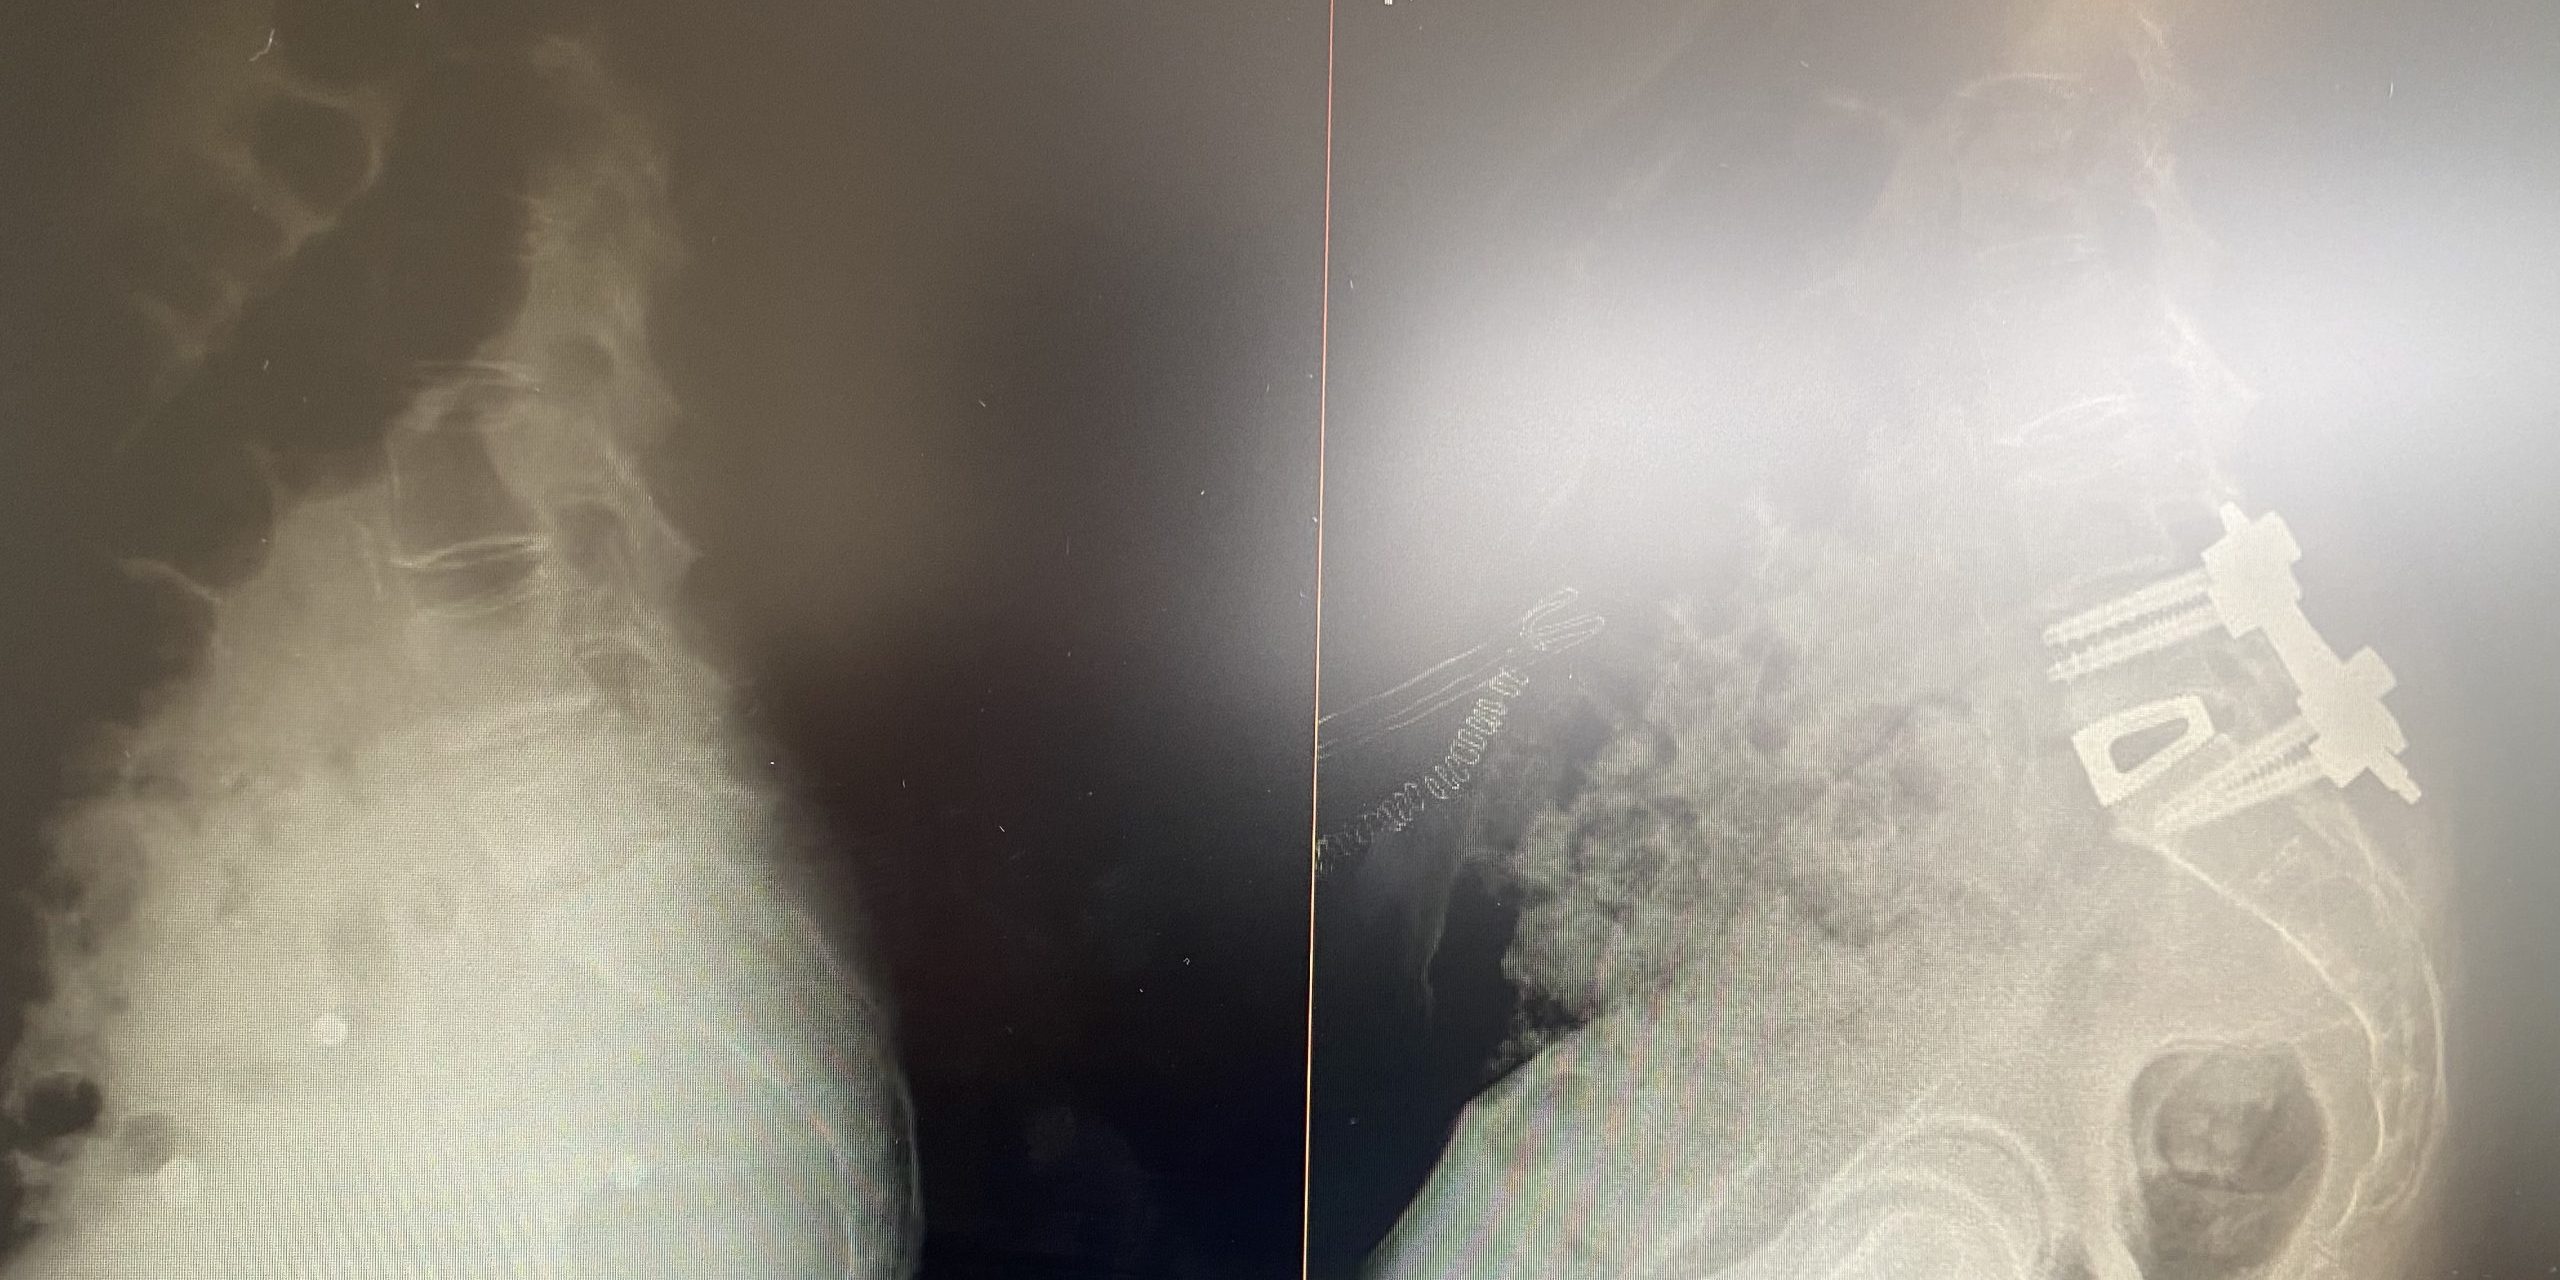

Es una variante, también mínimamente invasiva, de acceso a la columna lumbar que, en esta ocasión, accede al disco intervertebral desde delante. Normalmente se realiza una pequeña incisión lateral al ombligo. La musculatura abdominal es separada y el peritoneo (cavidad que contiene las vísceras abdominales) es rechazada lateralmente (no es necesario abrirla). Esto permite exponer la cara anterior de las vértebras y del disco. La ventaja de esta técnica es, además de su mínima invasión y su, por lo general, buena tolerancia para el paciente, proporcionar un camino alternativo, lo cuál puede ser de gran ayuda en paciente que, por ejemplo, ya han sido intervenidos previamente por la vía posterior habitual. Además, ofrece la posibilidad de colocar un implante de mayor tamaño y evitar tener que lidiar durante la cirugía con los nervios y la duramadre, que quedan alejados del abordaje. Su cirujano espinal puede pedir la ayuda de un cirujano general o vascular que le asista durante el abordaje, aumentando así la seguridad.